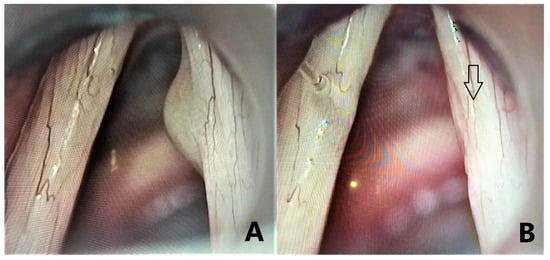

2.7. Surgical Procedure